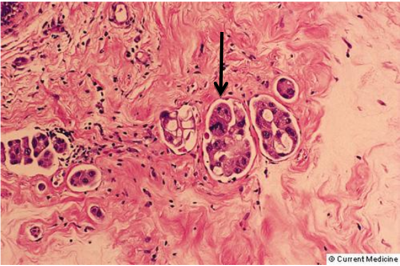

ב- 4% עד 40% מהשאתות שהוצאו במסטקטומיה (תלוי בסוג השאת) אפשר למצוא חדירה לכלי הדם או לכלי הלימפה (תמונה 34.12). הפרוגנוזה של החולים הללו היא פחות טובה מזו של החולים ללא חדירה כזו. בסקר על 20,000 נשים, נמצא שקיים קשר ישיר בין היוותרות בחיים לבין חדירת השאת לכלי הלימפה. כמו-כן נמצא קשר ישיר בעל אופי אקספוננציאלי בין מספר בלוטות הלימפה הנגועות לבין ההיוותרות בחיים וחזרת המחלה. המרכיבים הפתולוגיים המשפיעים על הפרוגנוזה מסוכמים בטבלה 8.12.

קיים קשר בין הסוג ההיסטולוגי לבין פוטנציאל הממאירות של השאתות. בקבוצה 1 נמצאות כל השאתות אשר אינן פולשניות: דוקטל קרצינומה מוגבלת לדאקט (In situ) ולובולר קרצינומה In situ (פאג'ט ללא נוכחות של גוש). בקבוצה 2 נמצאות השאתות שהן פולשניות, אולם שולחות גרורות לעתים נדירות, והן אדנוקרצינומה בעלת התמיינות טובה, מדולרי קרצינומה, קולואיד מוצינוס קרצינומה ופפילרי קרצינומה. בקבוצה 3 נמצאות כל השאתות השולחות גרורות במידה בינונית, כולן פולשניות (אינבזיביות) כמו ה- Infiltrating adenocarcinoma, דוקטל קרצינומה עם חדירה לסטרומה, Infiltrating lobular carcinoma וכל השאתות שאינן בקבוצות הקודמות. קבוצה 4 כוללת את כל השאתות השולחות גרורות בשכיחות גבוהה, כל השאתות שהן Undifferentiated ואת כל השאתות שחודרות מקומית לכלי הדם והלימפה (LVI - Lymphovascular invation) (תמונה 37.12).

- חדירה לכלי דם (שכיחות 40%-4%).

- חדירה לכלי לימפה.